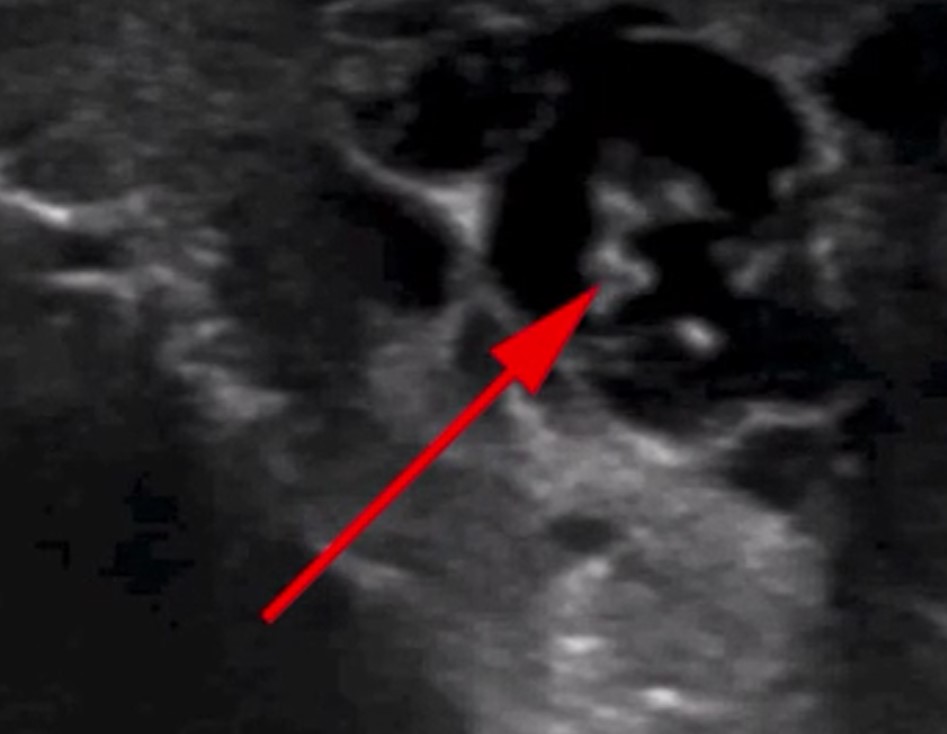

İngiliz Daily Mail gazetesinde yer alan habere göre, doktorlar hastanın skrotumunda hareket eden doğrusal yapılar keşfetti.

Nadir görülen enfeksiyon, New England Journal of Medicine tarafından yayınlanan bir vaka raporu ile ortaya çıktı. Hastayı muayene eden Max Süper Özel Hastanede kıdemli tıbbi danışman olan Dr. Amit Sahu, ultrasonda 'doğrusal yapıların hareket ettiğini' söyledi.

Sahu gözlemledikleri hareket eden doğrusal yapılar için 'dans edecen düzinelerce solucan' ifadesini kullandı. Sahu, 'Lenf sistemine göç ederek kanalların genişlemesine ve işlev bozukluğuna neden oldular' dedi.

Bu inceleme bilimsel olarak Wuchereria bancrofti olarak adlandırılan ve teşhisi doğrulayan canlı solucan ordularını gözler önüne serdi. Hastaya solucanları öldüren güçlü bir anti-parazitik ilaç olan dietilkarbamazin verildi.